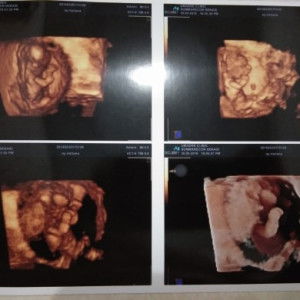

Saya hamil 9 minggu, apa boleh makan kerang?